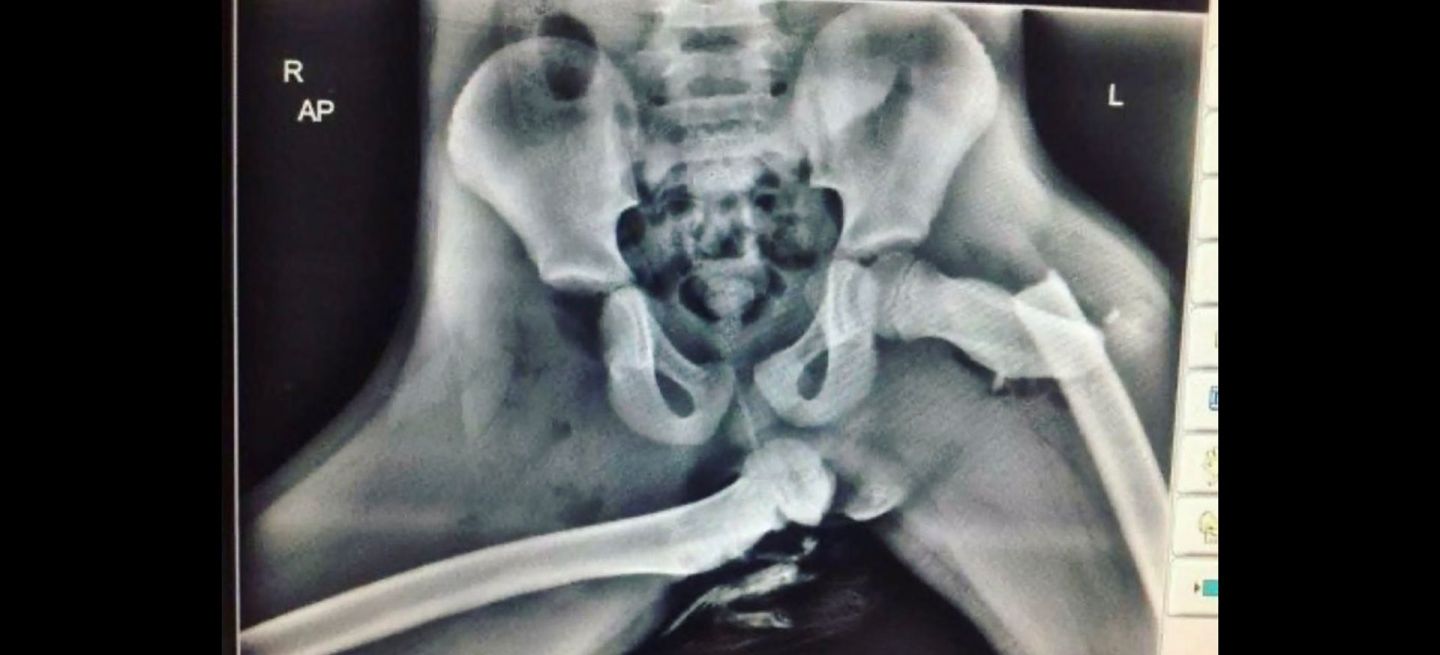

If you are the passenger, never put your feet on the dash. With or without airbags, don’t do it. Level 1 trauma hospital worker here. Seen a fatality of a passenger who had their legs on the dash during the collision. It literally shoved their (broken) leg back into them and their own leg bone (shard) pierced their chest cavity and heart.

Image of X-RAY from a person with feet on the dash in a SIMPLE collision.

Just image a hard one... pies-salpi...153270.jpg